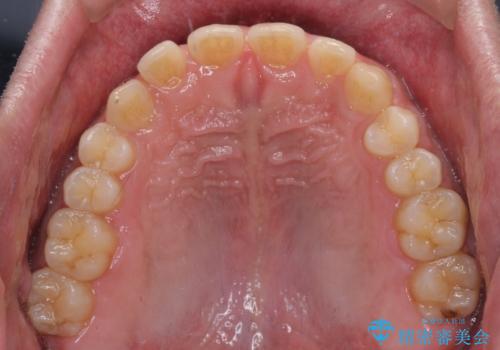

- 前歯の隙間と深い咬み合わせを改善したいとのことで来院された患者様です。

奥歯の咬み合わせは理想的な状態であったため、ワイヤー矯正でもインビザラインでも比較的容易に対応可能でした。